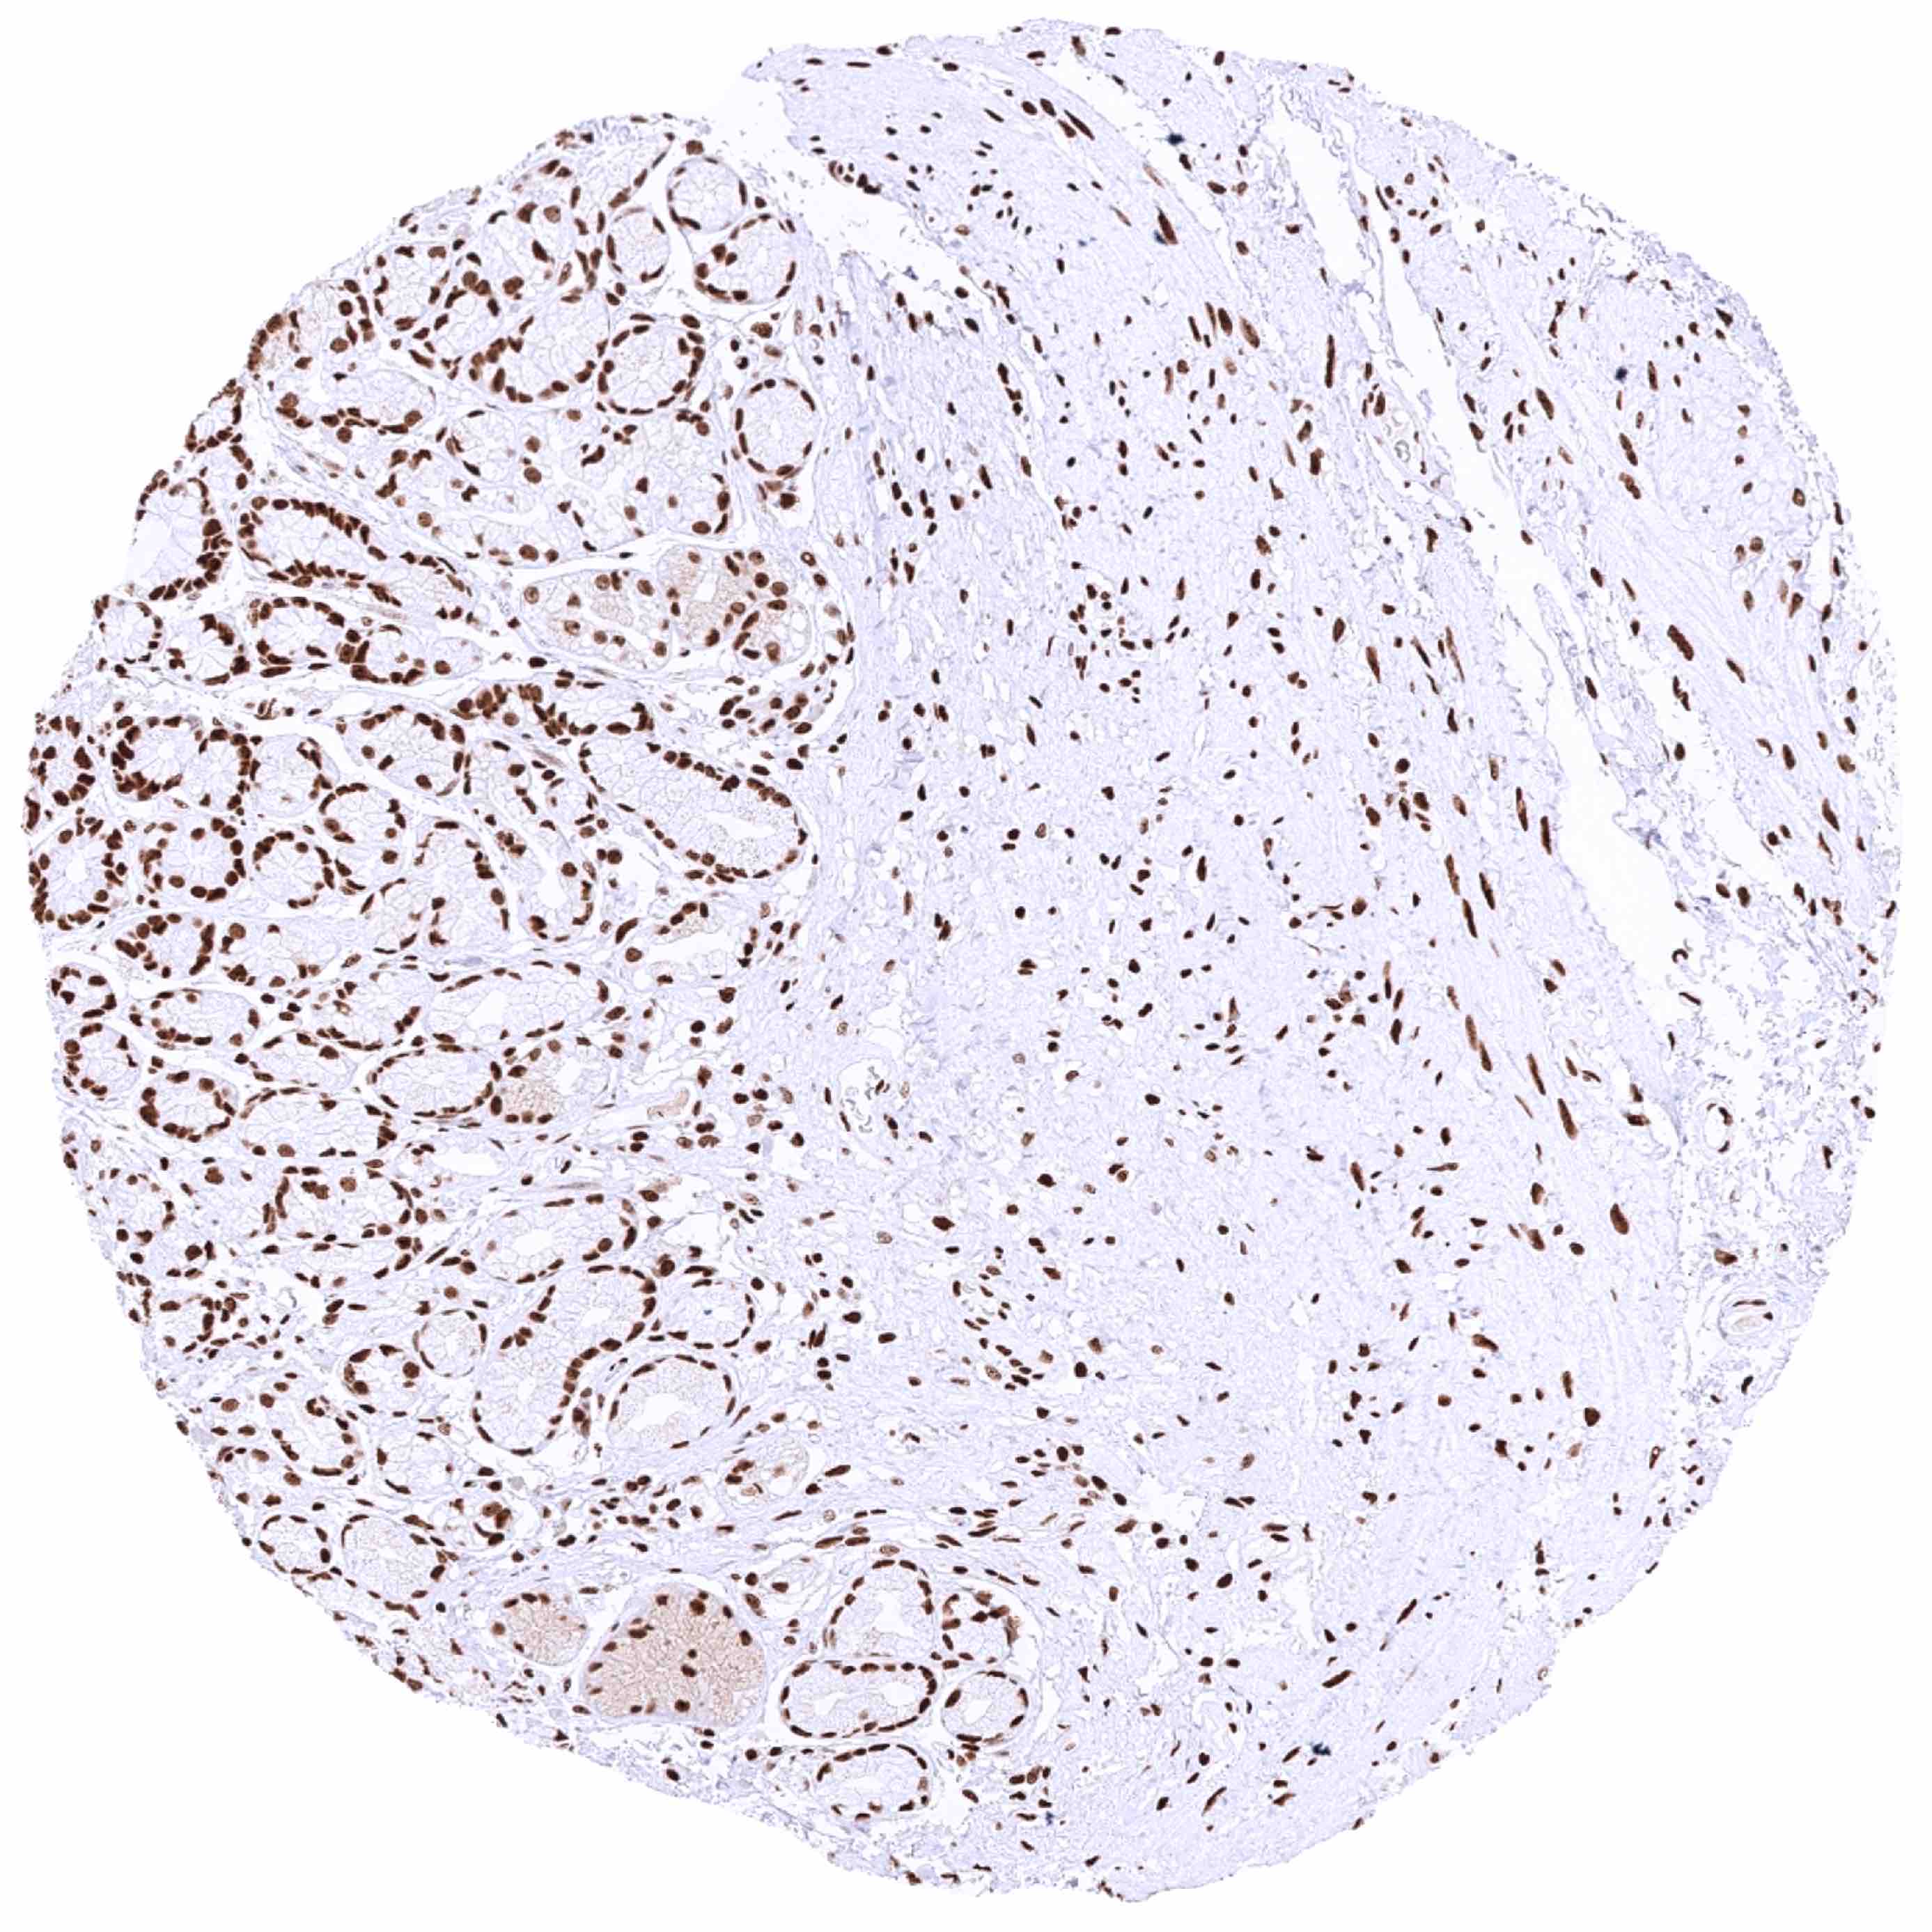

Kidney, cortex – Significant nuclear HMGB1 staining of all cells. Staining is particularly low in tubuli (especially proximal) and highest in collecting ducts and glomeruli